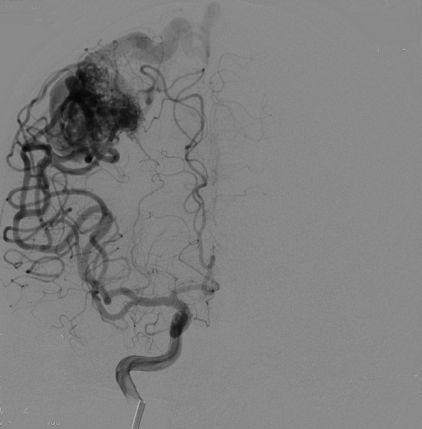

病例名称:颅内动静脉畸形的介入治疗 病史: 男性,62岁 主因“间断头疼半天”入院。 曝光模式及参数: DSA,减影3D 造影表现: DSA造影,造影提示右颈内动脉有巨大畸形血管团

为了观察动静脉畸形的栓塞效果,术后行DSA造影。DSA造影显示畸形团基本消失,栓塞效果较好